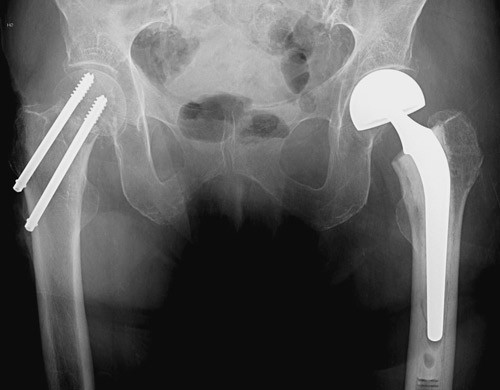

Osteosyntese

Det finnes over 100 forskjellige implantater for osteosyntese av lårhalsbrudd, men ingen er dokumentert bedre enn andre (18). Ved osteosyntese brukes det i Norge vanligvis to parallelle skruer eller nagler (4). Skruene eller naglene settes parallelt i lårhalsen, og en sammensynkning tillates for å komprimere i bruddet og med det øke sjansen for tilheling. Skruer er derfor gjenget bare i den delen som skal stå i caput femoris. To skruer eller nagler brukes for å hindre rotasjon (fig 1). Kvaliteten på reposisjonen er nok av større betydning enn typen skruer og nagler og deres plassering (18, 19). Forekomsten av osteosyntesesvikt er imidlertid nokså lik fra studie til studie, uavhengig av operasjonsmetode, type implantat og kirurgenes erfaring (6, 20) – (24). Selv med tilhelede brudd endres ofte anatomien og mekanikken i hofteleddet, særlig med forkorting av lårhalsen, slik at pasienten ikke får «sitt eget hofteledd» tilbake (6, 25).

Protese

Det skilles mellom hemiprotese og totalprotese. Ved en hemiprotese erstattes caput og collum femoris med en protese, mens acetabulum forblir urørt. I en bipolar hemiprotese er det et internt ledd i protesen, slik at en del av bevegelsen kan foregå der. I en unipolar hemiprotese foregår all bevegelse mellom protesehodet av metall og pasientens egen brusk i acetabulum. Ved totalprotese settes det også en protesedel i acetabulum. I Norge brukes bipolare hemiproteser i over 90 % av primære proteseoperasjoner ved akutt lårhalsbrudd, og over 90 % av disse igjen er sementerte (fig 1) (4, 10).